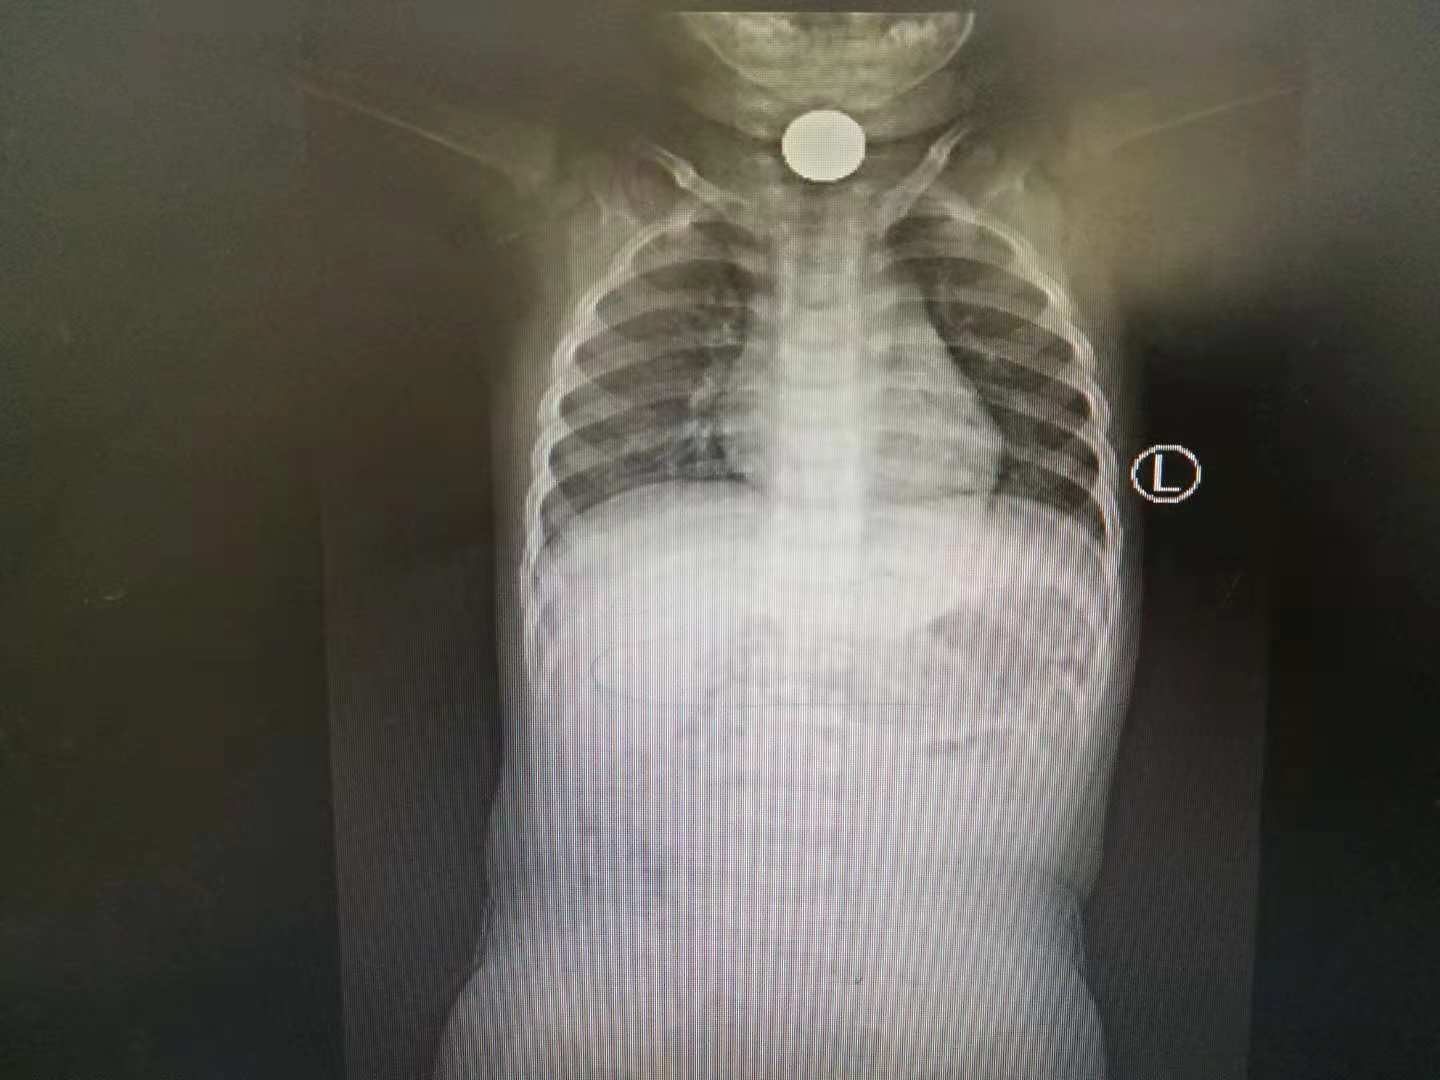

■硬币卡在食道里

“11月2日,光一天就接诊了两个这样的小病号。”李为介绍,“一个是在鼻腔里,塞进去了一个机器猫的小卡片,大约直径有1厘米左右。还有一个是耳朵里边进去了一个耳钉。”李为称,这些异物都是小孩子不小心弄进自己的鼻子还有耳朵里的。